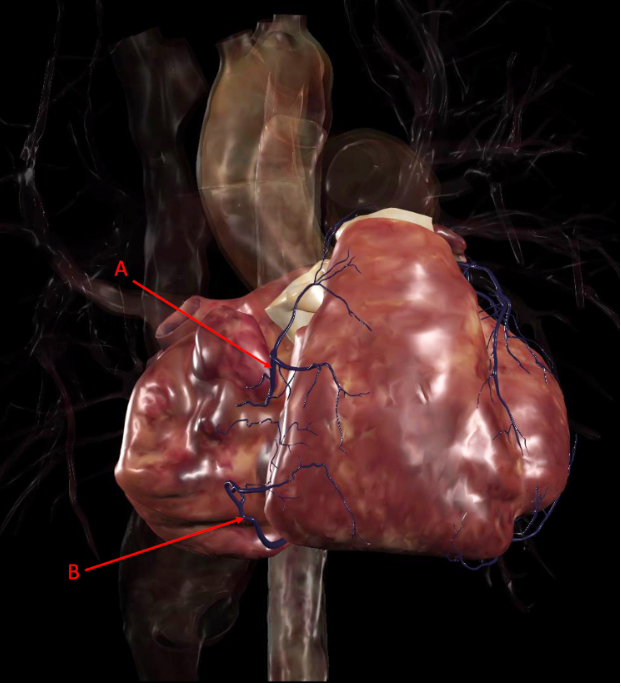

Q

Identify the following structure(s)

A

A. right coronary artery

B. right marginal artery